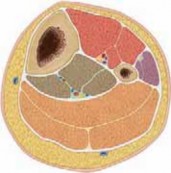

Chapter 16 Pediatric Tibial Fractures Craig P. Eberson DEFINITION Fractures of the tibia are common in childr…